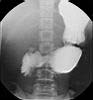

De dag voordien krijgt de patiënt een laxativum

zodat het colon zuiver is |